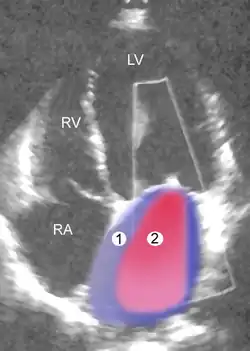

Mild mitral regurgitation. The colored cloud symbolizes the return blood flow. 1. left ventricle, 2. left atrium

Severe MR Legend

1 Left atrium (LA) – 2 MR Jet, LV Left ventricle – RV Right ventricle – RA Right atrium

An echocardiogram is commonly used to confirm the diagnosis of MR.[16] Color doppler flow on the transthoracic echocardiogram (TTE) will reveal a jet of blood flowing from the left ventricle into the left atrium during ventricular systole. Also, it may detect a dilated left atrium and ventricle and decreased left ventricular function.[6] A transesophageal echocardiogram can give clearer images if needed as the back of the heart can also be viewed.[17]